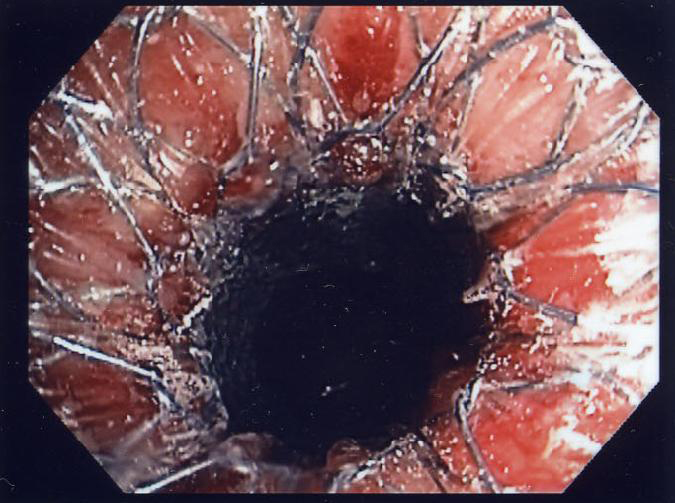

Endoscopic Mucosal Resection (EMR)

Endoscopic mucosal resection (EMR) is a technique use to remove small superficial cancers. Prior to EMR, your gastroenterologist can perform endoscopic ultrasound to be certain the cancer is superficial. These decisions are also made in conjunction with a thoracic surgeon.

Removal of the superficial cancer with EMR is accomplished by placing a small rubber band around the tissue after it has been suctioned into a cap at the end of the endoscope. Once the area of concern has been banded, a "snare" is inserted and closed around the tissue. Electrocautery (heat) is then applied through the metal snare to cut the tissue out of the esophagus. The area is then allowed to heal, and in a few weeks, it is re-inspected with upper endoscopy and biopsied to ensure that all abnormal tissue has been removed.